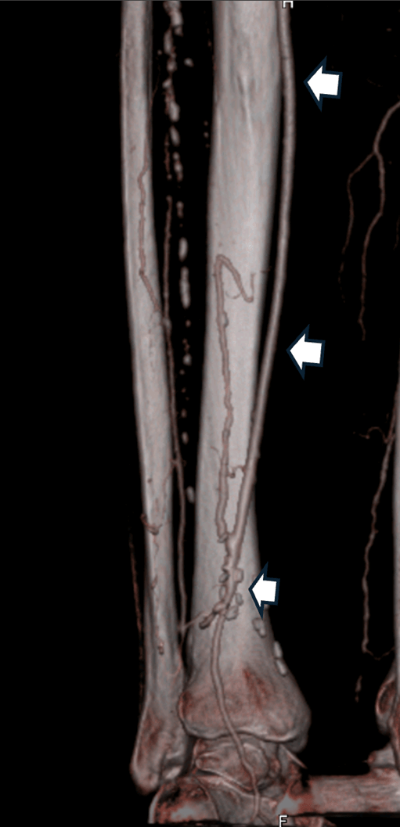

- Cirurgia de bypass: s’utilitza un empelt (vena pròpia del pacient o un conducte artificial) per desviar la sang i superar l’obstrucció (Fig. 2)

Fig. 2: Bypass distal a nivell del turmell, amb vena safena del mateix pacient (fletxes blanques).